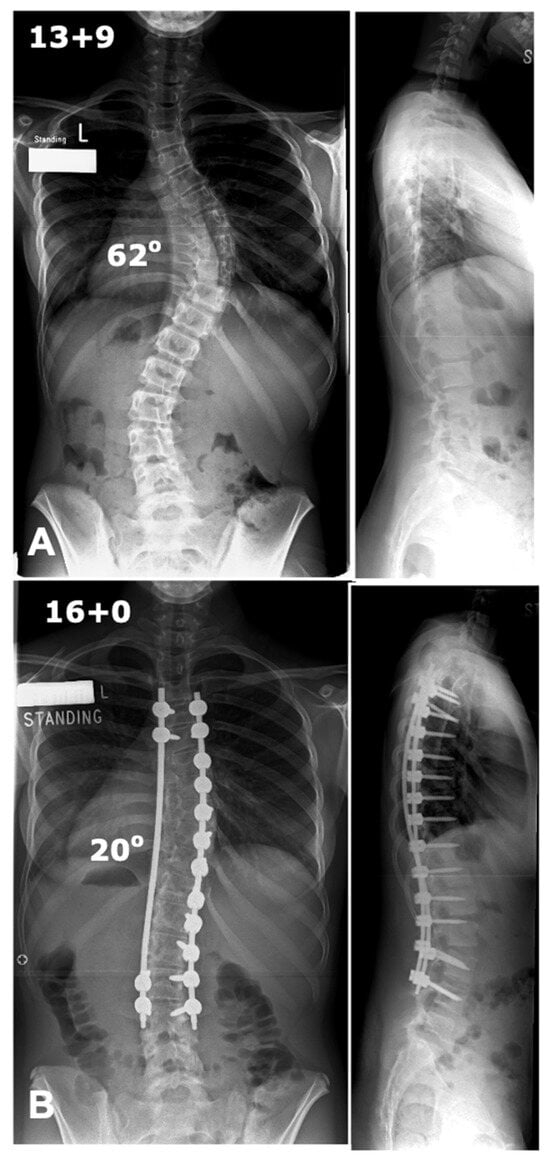

The global rod derotation technique, originally introduced by Cotrel and Dubousset, is based on the concept that the coronal deformity typical in AIS approximates the desired sagittal alignment when rotated 90° [51]. This method involves inserting a rod pre-contoured to the ideal sagittal shape on the curve’s concavity. The anchors are loosely attached to the rod and then rotated 90° along the axial plane to transform the coronal deformity into sagittal alignment [52,53]. The traditional use of the concave side for scoliosis correction poses challenges due to anatomical constraints. Studies, including that by Liljenqvist et al., reveal significantly narrower pedicles on the concave side at the thoracic curve apex, increasing the risk of cortical wall penetration [54]. Anekstein et al. evaluated the use of a convex rod derotation technique for correcting AIS in 40 patients treated with all-pedicle screw constructs and followed for two years. The mean preoperative Cobb angle of 60° improved to 17° postoperatively, with a 7% correction loss at follow-up, yielding a 71% major curve correction. The technique showed comparable outcomes to traditional concave-side corrections, with additional benefits of reduced neurological risks due to safer screw placement on the convex side. Thoracic kyphosis decreased slightly, and no major complications, infections, or revisions were reported [55]. This approach benefits from the stability offered by multiple fixation points, distributing mechanical stress and reducing localized anchor strain. It is particularly effective for thoracic hypokyphosis, enabling simultaneous correction in both the coronal and sagittal planes. However, this technique does not correct axial plane deformities. Advanced imaging has shown that while previously thought to induce rotational correction at the apex, it primarily results in translational adjustment. Additionally, the ideal sagittal contour may not align with the coronal deformity, potentially leading to suboptimal sagittal apex placement post-rotation [46,56]. A case example is shown in Figure 2.